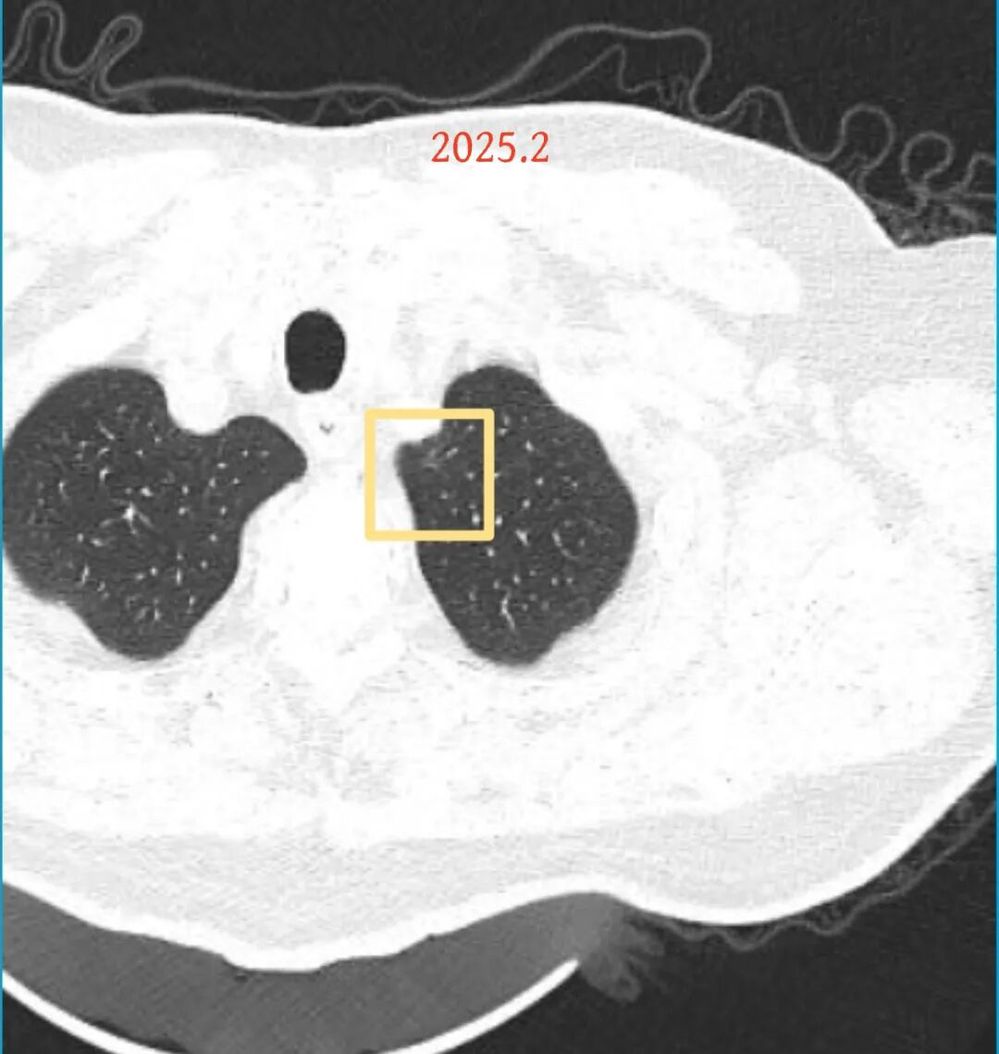

方形的是25年的,红色的主病灶,磨玻璃密度伴少许略偏高点密度,但还说不上典型混合磨玻璃病灶,考虑原位癌或微浸润性腺癌可能性大;蓝色的轮廓与边界欠清,位置靠上叶中央,无法段切或楔切;黄色的多发均淡而纯,分布在两肺。圆形粉色的是主要的两处23年时的样子,对比说不上很明显进展。鉴于若手术得切肺叶,何况两肺他处仍的结节,年纪又74了。我倾向保守点,先6-9个月复查,等进展并风险增加再来考虑怎么办的事。意见供参考!

我的想法是主病灶在右上叶,且多发,而且位置较深,若手术很可能要切且叶,虽考虑是肿瘤范畴的,但由于不管病灶A还是病灶B均仍是磨玻璃密度,没有纵隔窗可见的实性成分,在两肺多发病灶的情况下,适当保守点再随访下,待有进展并风险增高再干预也不至于影响预后。而且根据既往经验,磨玻璃密度的肺癌基本太会短时间内快速进展。

病灶B似乎灶内有少许密度略偏高,但瘤肺边界欠清晰,总体说不上太显著的进展。

右肺上有两处病灶,仍然是磨玻璃密度,整体轮廓较为清楚,对比23年的说不上非常明显的进展。确实需要考虑微浸润性腺癌可能性大(上次我也说原位癌或者微浸润性腺癌)。主要纠结于位置太靠中间,如果手术基本上得切除右肺上叶。我的想法是已经75岁的年纪,如果进展很慢的话,是不是也不是一定得开刀。或者随访看它进展情况,到时候再来考虑。个人稍微倾向于仍然六到九个月复查,有进展并风险增加再手术,或者其他方法干预。意见供参考!

当时结友自己还觉得有点实性成分,血管感觉也有增粗。而我觉得整体密度仍是磨玻璃,轻微的变化仍不足以影响临床决策的程度。

病灶没有确切纵隔窗可见的实性成分,但与血管关系较为密切。

再看2026年3月最近复查时不同层面病灶A的细节影像特征:

微小血管走向病灶,磨玻璃的密度淡而较纯。

再看病灶B的2026年3月细节影像特征:

边缘位置也是较淡的磨玻璃成分。

上图是混合密度,轮廓较清,瘤肺边界欠清晰。

病灶A以及他处磨玻璃结节其实进展都是不明显的,略与2022年比,病灶A稍显明显点。病灶B开始时极淡,之前进展虽有但也甚微,直到2025年9月仍是磨玻璃成分为主,只是点状少许密度稍高成分。但在最近半年内却显然进展!若从影像上判断,基本上就得是浸润性腺癌了。那有几点:一是必不能再随访;二是大小来看仍是1A期;三是从快速进展来说,可能含有部分高危亚型,比如微乳头或实体型等;四是他处的磨玻璃结节以及病灶A显然不能用病灶B的转移来解释,仍考虑是多原发早期肺癌。

结友问能否先穿刺?我是这么考虑的:你这个病灶B一是位置深,且靠近附近的血管,不容易穿刺;二是从影像变化来看,基本上肯定是恶性的,不是100%,也是95%以上的概率。刚才我又在重建看冠状位与矢状位以及各次影像,目前混合密度的其实是后来者居上,原来刚开始是它比旁边的病灶密度淡的,但它的密度不是太纯,前次你自己也说似乎有点状偏实性成分。只是最近这半年进展特别快。这说明它的恶性程度较它边上原来就比较明显的那处恶性程度高,亚型中大概率有低分化的成分。所以从目前的影像来看,要尽快手术,而且切肺叶更为稳妥些。

这是较为少见的一个病例,磨玻璃为主,而且一直瘤肺边界欠清晰的病灶何以会在之前三年均极缓慢微小变化的情况下,近半年却快速进展呢?从影像细节上看,我们能否进一步分析哪种纯磨玻璃结节可能会较快进展?结合本例,我个人的考虑是:1、病灶整体显得是磨玻璃密度,但灶内并不均匀,就如磨玻璃密度中混入细沙状;2、整体轮廓虽然较清但瘤肺边界相对来说却并不太清晰;3、邻近有血管紧挨,而且与病灶这间缺乏间隙;4、病灶密度不高,没有明显实性成分,却有灶内有细支气管通气征,说明肿瘤成分具有收缩力,却与纯磨的收缩不匹配(纯磨一般不太会有明显收缩力)。如果有上面这些特征可能要提高警惕,一是适当较短的随访间隔,二是影像细节变化要更加注意,开始变化意味着已经进入发展期,而非蛰伏期。当然是否在2025年9月时定得手术了?如果是孤立性的病灶B,且位置位于能简单楔形切除的位置,那是可以考虑的。但位置深、两肺多发,切除范围不小,再今年据肺癌诊疗指南中说的混合磨玻璃结节实性成分不足25%是非侵袭性病变,且几乎不会转移,那么按原则仍再随访显然是可以的。本例的随访变化再次表明磨玻璃密度肺癌的诊疗个体化之路仍是很漫长的,按指南原则的随访或诊疗显然不足以覆盖所有病例,总结与经验积累永远在路上。